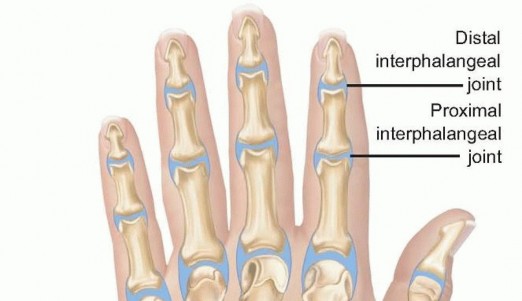

The extensor mechanism overlying these joints is highly susceptible to iatrogenic injury during surgical drainage. At the MCP level, the extensor tendon is centralized by the sagittal bands. Dorsal approaches must carefully split or retract these structures without compromising their stabilizing function. At the proximal interphalangeal (PIP) joint, the extensor mechanism divides into the central slip (inserting on the middle phalanx) and the lateral bands (converging to form the terminal tendon at the distal phalanx). Disruption of the central slip during a dorsal approach to the PIP joint will inevitably lead to a boutonniere deformity, while injury to the terminal tendon results in a mallet finger.

- The Midaxial Approach: For the PIP joint, a midaxial approach is often preferred over a direct dorsal approach to avoid injuring the central slip. The midaxial line is identified by connecting the apices of the flexion creases. An incision is made along this line.

- Neurovascular Protection: The dissection proceeds volar to the lateral band of the extensor mechanism but dorsal to the neurovascular bundle. Cleland's ligaments may need to be divided to mobilize the neurovascular bundle volarly.

- Capsular Access: The transverse retinacular ligament is incised, and the collateral ligament is identified. The joint capsule is incised dorsal to the collateral ligament, allowing access to the joint space for thorough irrigation and synovectomy.

- DIP Joint: The DIP joint can be approached via a similar midaxial incision or a dorsal H-shaped or Y-shaped incision, taking absolute care not to disrupt the terminal extensor tendon insertion on the distal phalanx.